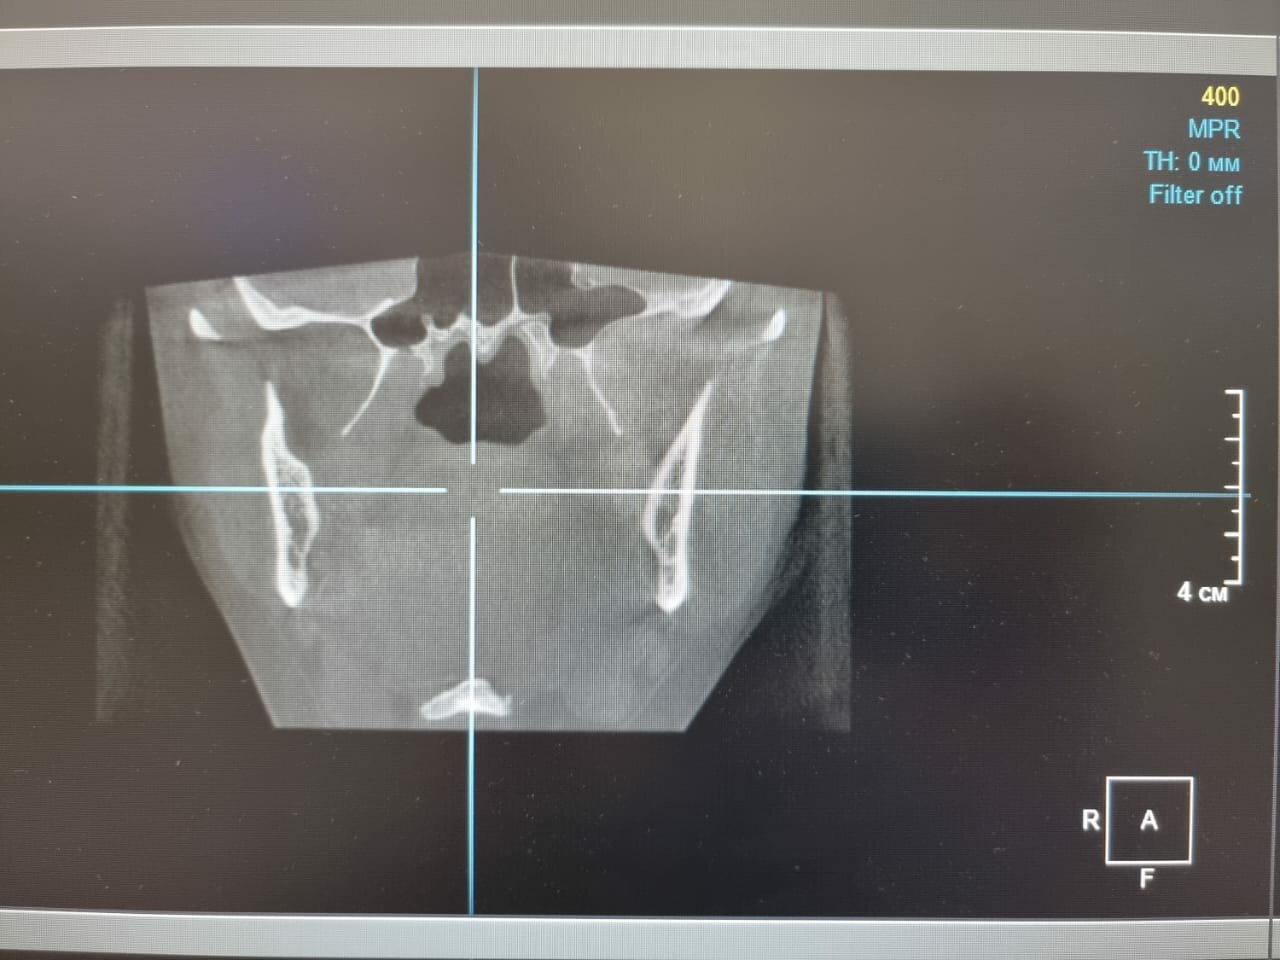

Основные направления работы клиники: общая стоматология (лечение кариеса, гигиена, удаление зубов), ортодонтия (брекеты, элайнеры), хирургическая стоматология (имплантация, челюстно-лицевые операции), эстетическая стоматология (виниры, отбеливание, реставрация) и детская стоматология. В клинике используются передовые технологии, включая лазерную стоматологию, компьютерную томографию и цифровую диагностику, что обеспечивает безболезненное и эффективное лечение.

- рентгенография

- Современное оборудование и качественный ремонт.